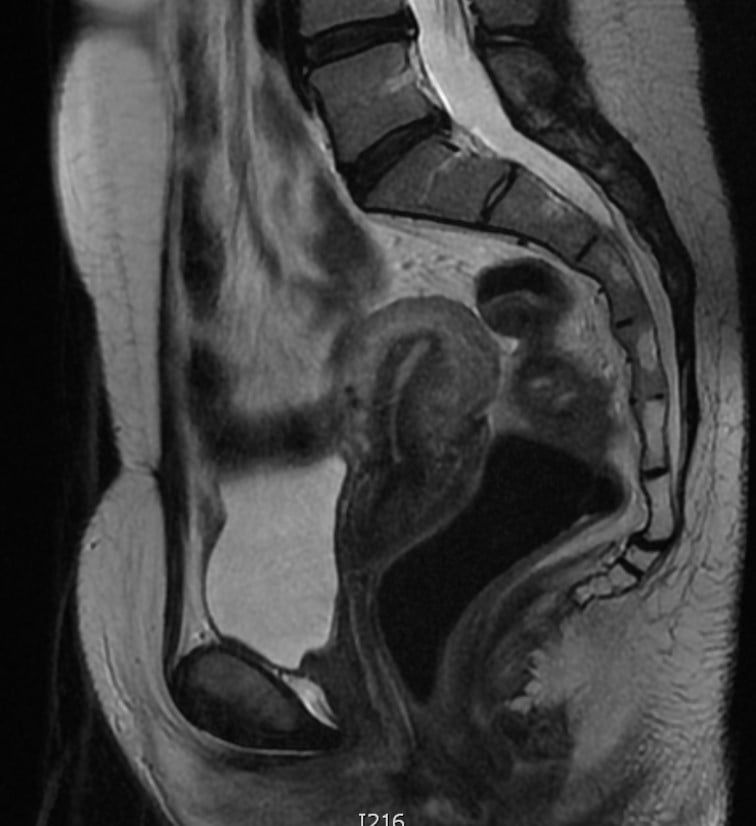

Pelvic MRI (Figure 3) and endovaginal ultrasound found no other endometriotic lesions in the pelvis. According to patient preference, hormonal therapy was started and symptoms remission was achieved.

Figure 3. Pelvic MRI: coronal (left) and transverse (right) planes. Rectosigmoid endometriosis, with no other endometriotic lesions in the pelvis.